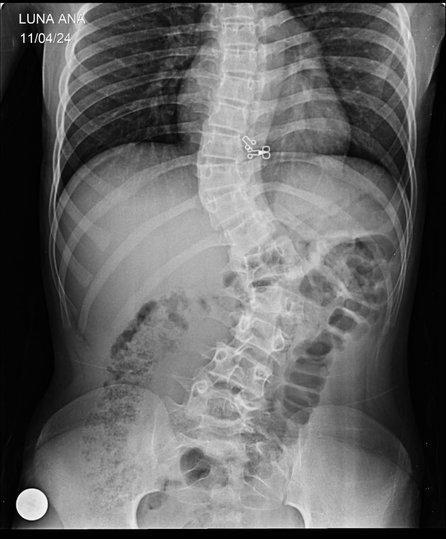

La menor fue diagnosticada con escoliosis congénita en el hospital Materno Infantil, donde los profesionales pueden operarla pero la familia de Ana Gabriela debe proveer la prótesis y otros insumos.

El diagnóstico habla de una escoliosis congénita, una curvatura que va de lado a lado de la columna vertebral y que está presente al nacer, la cual no fue detectada sino hasta ahora.

Estando en Salta, contó que le hicieron múltiples estudios, resonancias, tomografía y otros tipos de radiografías y ahí le diagnosticaron que tenía escoliosis congénita, que viene desde el nacimiento. "Este tipo de escoliosis no presenta dolores, lo que es algo raro y por eso, nunca nos dimos cuenta que ella vino con ese afección desde que nació”, contó.

“Le tienen que realizar una cirugía que va desde la cervical hasta el coxis y tienen que sacarle tres vertebras para poder enderezarle su columna. Y en Acción Social de Salta, de la parte del Materno Infantil, me dijeron que los insumos les va a hacer imposible conseguirlos porque el Gobierno Nacional no está enviando los insumos por los recortes que hay, entonces, tengo que conseguirlos yo, eso incluye las varillas de cromo y titanio que son las que van de punta a punta por la columna, justamente para poder enderezarla”, señaló.